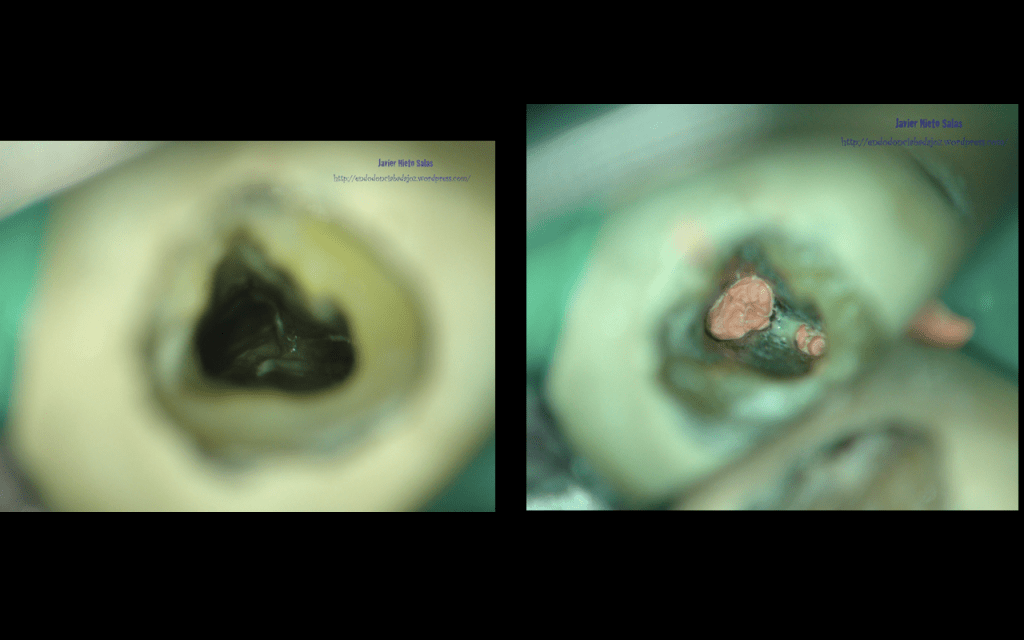

Trabajar bajo la magnificación hace que entendamos un poco mejor el complejo sistema de conductos, nos ayudará a su preparación ,tanto química como mecánica, y nos hará entender la necesidad de aplicar condensación vertical para conseguir un mejor sellado.

Con lo que, después de tallar los conductos, activar el hipoclorito, pasamos a la obturación, que como hemos adelantado, la realizamos con condensación vertical con la técnica de ola continua de Buchanan, y un backfilling con gutapercha inyectada.